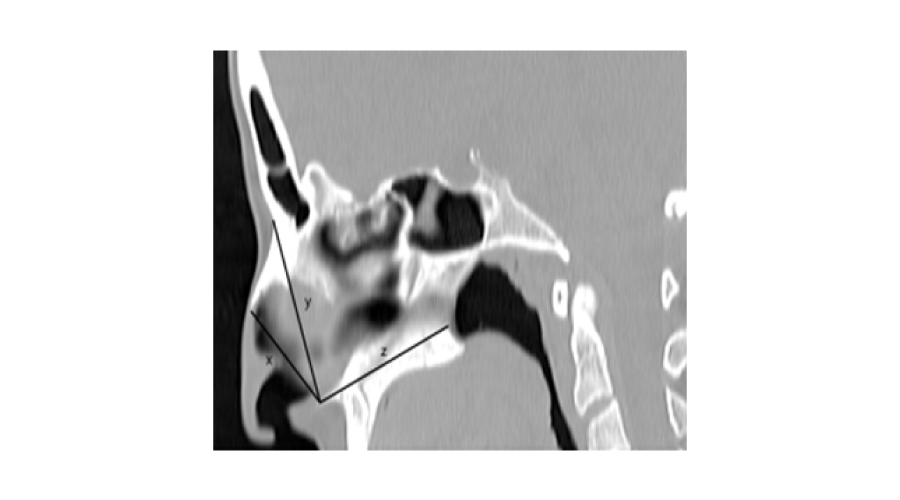

The width of the pyriform aperture (PAW) was defined as transvers distance between the right and the left frontal process of maxilla where it was the first appearance of inferior turbinate bone on the coronal planes. At the same section, the distance between the right and left frontal process of maxilla to anterior nasal spine was regarded as right maxillospinal length (RMSL) and left maxillospinal length (LMSL), respectively (Figure 1).

Figure 1:

1. The following parameters on the midsagittal images were measured (Figure 2)The height of the pyriform aperture (PAH): the distance between the lowest point of the nasal bone and anterior nasal spine.